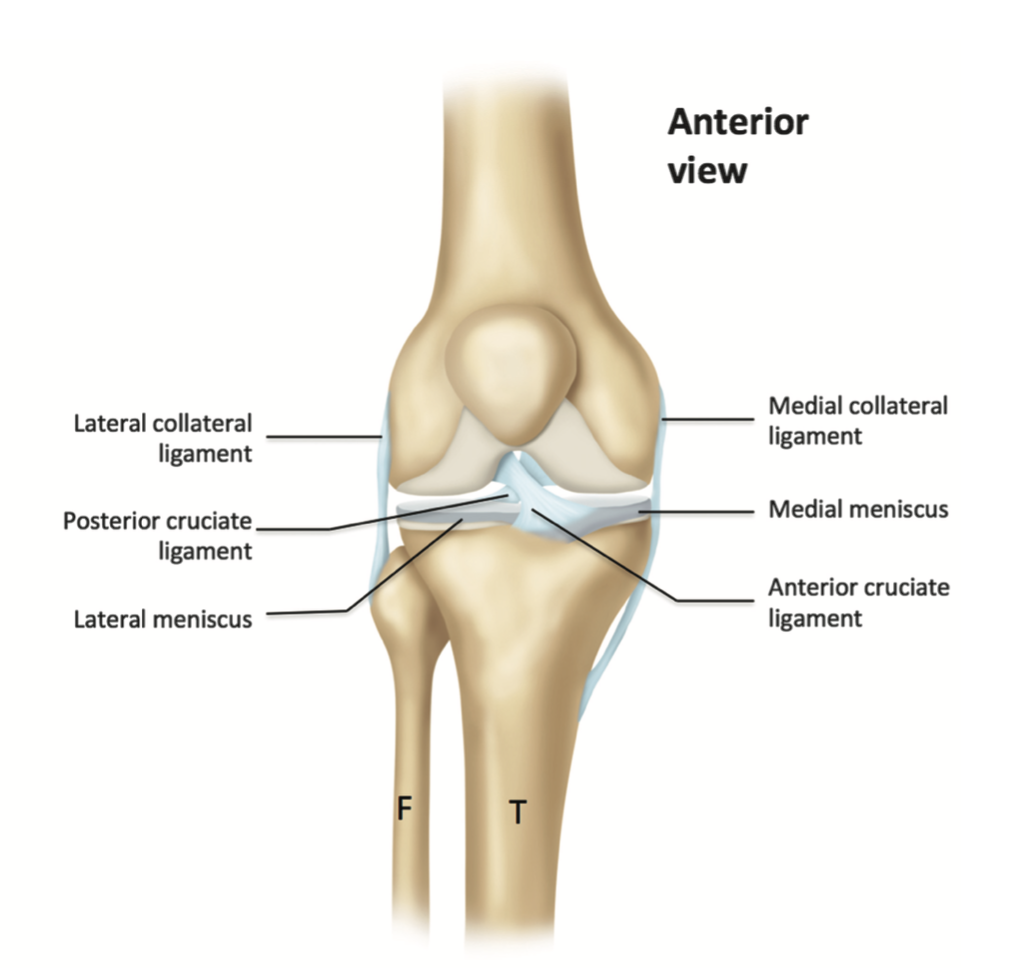

What does the medial collateral ligament reveal when the ultrasound probe is placed over its long axis?

A

Superficial layer and the deep meniscofemoral and meniscotibial components.

Going down to Tibia insertion: Pes anserinus complex inserting into the anterolateral aspect of the tibial metaphysis. At this level, the 3 tendons of sartorius, gracilis, and semitendinosus cannot be differentiated from each other.

What appears as a hyperechoic triangular structure between the femur and tibia?

Medial meniscus.

9

Q

Which tendons blend together to form the pes anserinus complex?

Sartorius, gracilis, and semitendinosus.